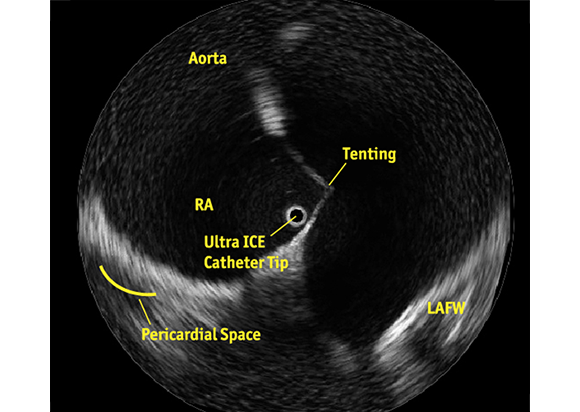

Know Where You Are

ULTRA ICE PLUS catheter positioned in the right atrium, adjacent to the fossa ovalis, visualizing the structures critical to successful transseptal puncture: the septum, aorta, needle position, tenting, and the LAFW.